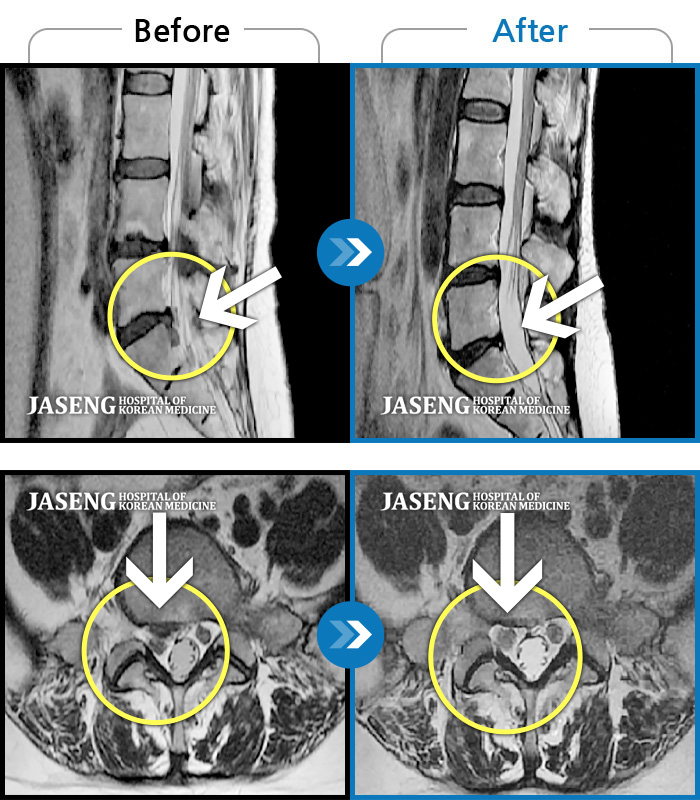

김상돈 원장님 칭찬 드립니다 대학병원,척주질환 전문 병원에서 목디스크 수술 진단을 받았었는데 지인 추천으로 자생한방병원을 방문 했었는데 김상돈 원장님께서 친절한 설명과 성심성의 치료를 해주신 덕분에 일상 생활을 정상 적으로 하고 있습니다 원장님 감사합니다

내일이면 퇴원이다. 3월부터 주위에서 허리통증 치료 잘 한다는 통증의학과ㆍ신경외과ㆍ정형외과 병원 3곳을 돌아다니며 허리 신경주사 12번 ,도수치료 10번, 물리치료 등등 정알 여러가지를 받았다. 그러나 치료와 처방 받은 진통제만으로는 일상생활을 하기가 많이 힘들었다. X레이 사진으로 확인한 척추 전방전위증은 결국은 수술을 받아야 한다고 하였다.

전방전위 대해 알아보다가 자생병원 홈페이지에서 김상돈 병원장님이 임상치료 하셨다는 것을 보고 잠시의 망설임도 없이 전화 예약하고 입원 하게 되었다.

MRI 검사로 정확한 진단을 시작으로 병원장님의 치료를 2주간 받았다. 친절한 설명과 따뜻한 배려로 정말 마음 편하게 치료 받을수 있었다.

극심한 통증으로 입원 첫날에 맞은 진통제 주사는 더 이상 필요없게 되었다 다시한번 김상돈 병원장님께 감사 드립니다.